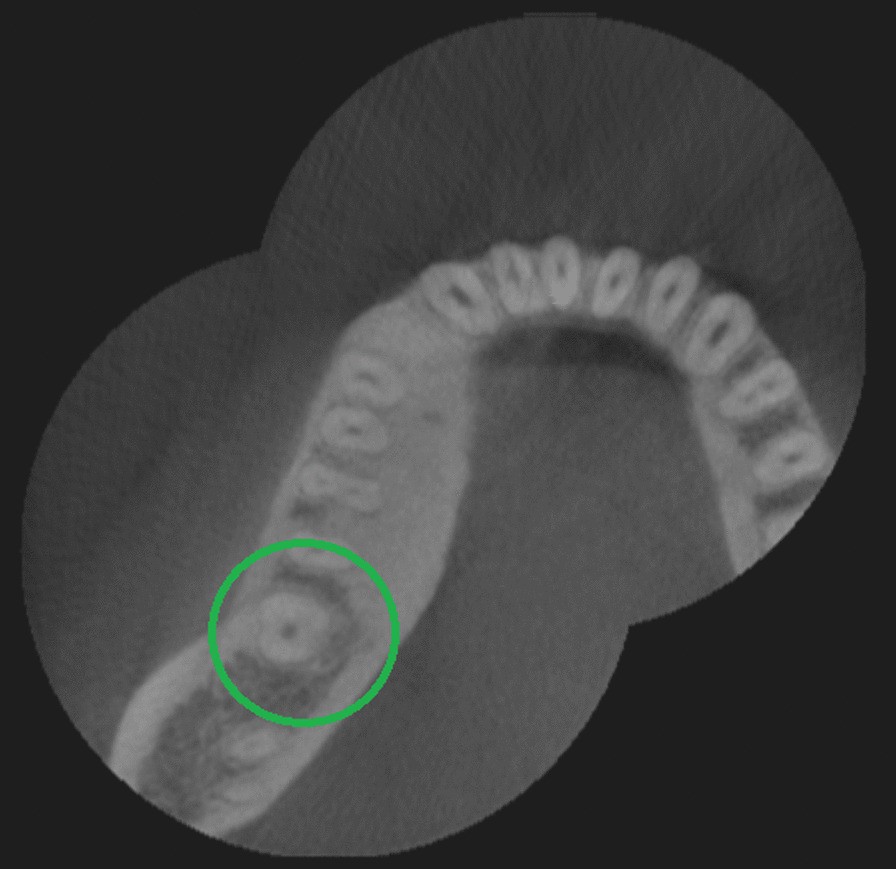

Fig. 2From: Root canal morphology and variations in mandibular second molars: an in vivo cone-beam computed tomography analysisAxial view from CBCT scan showing mandibular second molar with one rootBack to article page